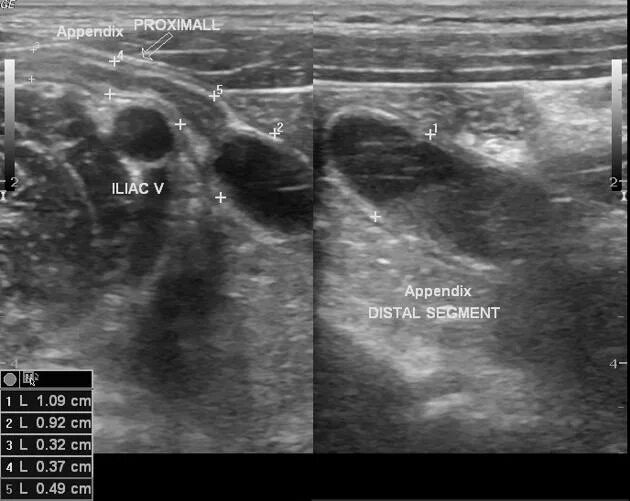

Аппендицит на узи можно ли